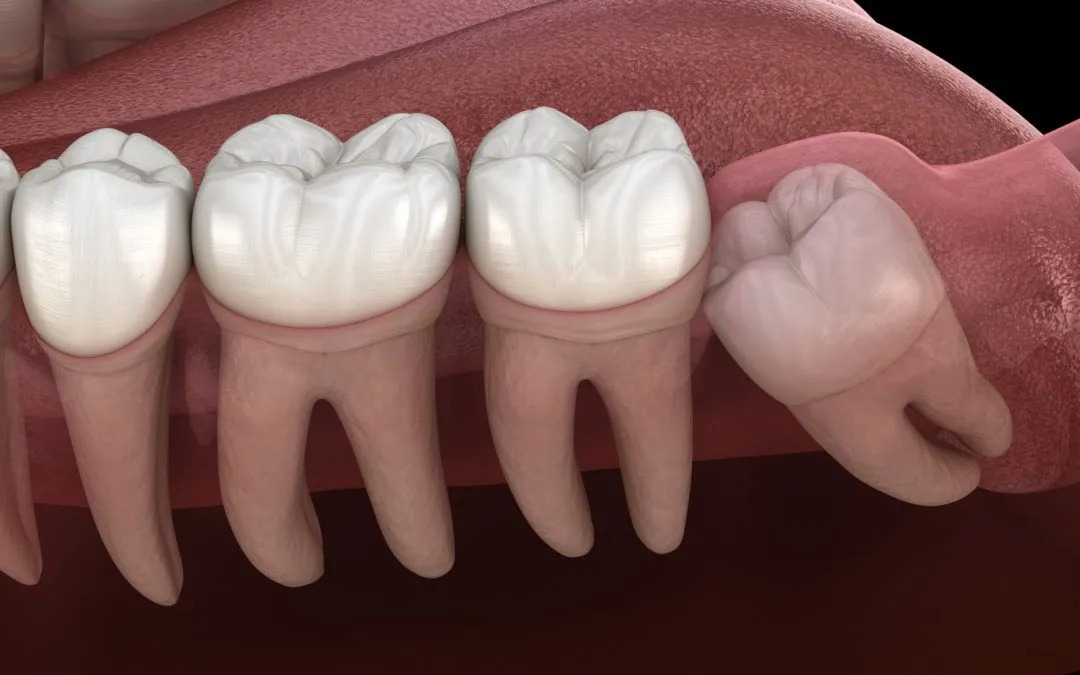

Wisdom teeth, or third molars, typically emerge between ages 17-25. While some people experience no issues, many face pain, swelling, and misalignment due to limited space in the jaw. Impacted wisdom teeth—those that cannot fully emerge—can lead to infections, crowding, or cyst formation.